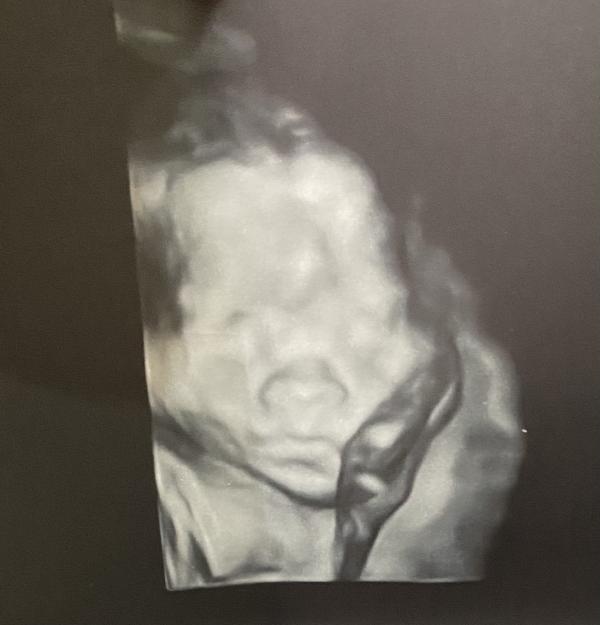

Наша история началась 11 ноября 2021 года, когда на 1 скрининге в 1 роддоме на сроке 12 недель,нам с мужем сообщили , что у ребёнка обнаружена патология «Крестцово-копчиковая тератома»